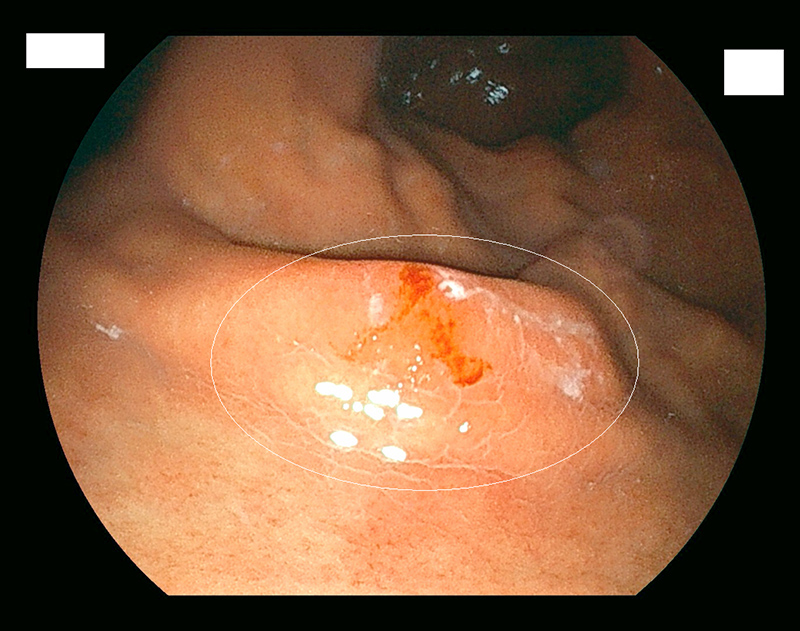

大腸ポリープ

通常光(白色光)

通常光では淡い発赤ですが

特殊光-1

同じところを空気量調整し特殊光LCIにて観察

特殊-2

同じところを特殊光BLIにて血管と表面構造を観察

IS型といわれる大腸ポリープです。

スネアをポリープに引っ掛けます。

スネアの輪を絞ります。

ポリープを切除、血液のにじみはわずかです。